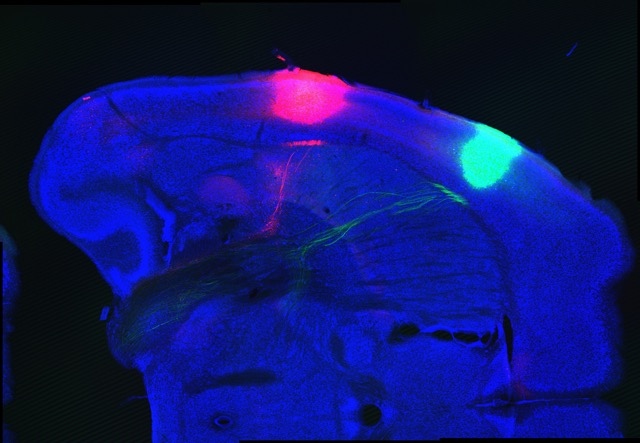

En el nuevo estudio, el equipo de Zuker utilizó optogenética, lo que permitió a estos científicos activar directamente neuronas específicas con luz láser. Yueqing Peng, del equipo de investigación, examinó si manipular las neuronas en estas regiones del cerebro puede suscitar la percepción de lo dulce o lo amargo, sin que el ratón estuviera saboreándolos realmente. (Se eligieron los sabores dulce y amargo porque son los más esenciales y reconocibles para los humanos y otros animales. El sabor dulce permite identificar nutrientes ricos en energía, mientras que el amargo advierte contra la ingestión de sustancias potencialmente nocivas.)

Esto es exactamente lo que observaron los investigadores. Cuando inyectaron una sustancia en los ratones para silenciar las neuronas del sabor dulce, los animales no podían identificarlo debidamente. Sí podían, sin embargo, detectar el sabor amargo. Los animales recuperaron su habilidad de detectar el sabor dulce la sustancia desapareció de su cerebro. Al contrario, silenciar las neuronas del sabor amargo evitó que los ratones lo reconociesen, pero aún podían saborear lo dulce.

Más espectacular aún resulta el hecho de que los científicos lograron hacer que los animales creyeran estar probando algo amargo o dulce incluso cuando estaban solo bebiendo agua pura y normal. Cuando activaron las neuronas del sabor dulce mientras los ratones bebían, observaron respuestas de comportamiento en ellos asociadas con este sabor, como lamer mucho más. En cambio, estimular las neuronas del sabor amargo redujo drásticamente esta operación, y ocasionó respuestas clásicas de rechazo ante algo de mal sabor, incluidas las típicas arcadas provocadas por el asco.